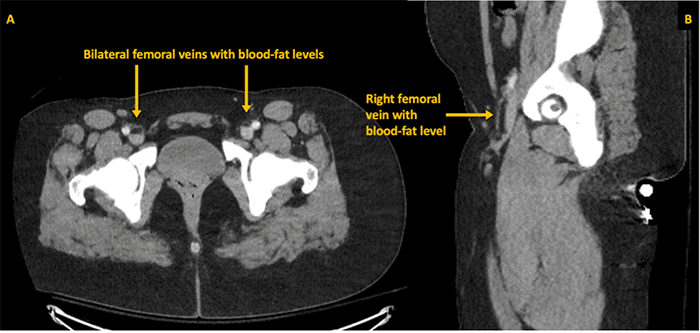

Approximately six hours after admission to the TSICU, the patient experienced an acute neurological deterioration, manifesting as right upper extremity (RUE) weakness and dysarthria. Urgent magnetic resonance imaging (MRI) of the brain was performed, which demonstrated diffuse small vessel ischemic infarcts affecting bilateral cerebellar hemispheres (Figure 3), presumed to be secondary to paradoxical fat embolization. This diagnosis was further supported by an emergent transthoracic echocardiogram, obtained immediately following the MRI, which identified a Grade 1 patent foramen ovale (PFO) (Figure 4). In light of these findings and to mitigate further propagation of fat emboli from the unstable femur fractures, the patient was taken emergently to the operating room by the Orthopaedic Surgery service for bilateral femoral external fixation, serving as a damage control measure until she achieved greater neurological stability.

Figure 4. Echocardiographic Evidence of Patent Foramen Ovale. Published with Permission

The image captures the appearance of microbubbles (arrow) within the left ventricle shortly after opacification of the right heart chambers, confirming a right-to-left shunt consistent with a PFO